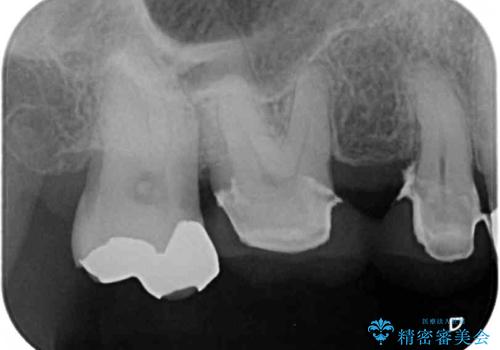

咬み合わせにより発現した歯周ポケットに汚れがたまり、歯周病のような状態になってしまっていました。

失われていた歯槽骨を、再生治療により可及的に改善させ、その1年後に歯周ポケットを除去するための歯周外科処置を行うこととしました。

歯槽骨の再生には1年ほどの待機期間を要し、その後のポケット除去処置も数か月の待機期間を必要とするため、治療期間は長期に及びました。